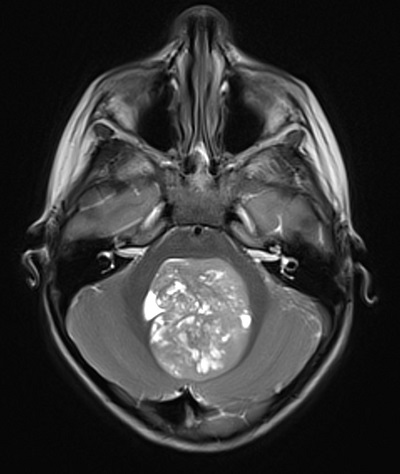

Se deriva a Urgencias Pediátricas, donde se realiza RMN craneomedular (Fig. 1) que objetiva una masa de 5 cm de diámetro localizada en el cuarto ventrículo, moderada hidrocefalia y edema transependimario acompañante, sugestiva de meduloblastoma.

| Figura 1. RMN craneomedular que objetiva RMN craneal: una masa de 5 cm de diámetro localizada en el cuarto ventrículo, moderada hidrocefalia y edema transependimario acompañante, sugestiva de meduloblastoma |